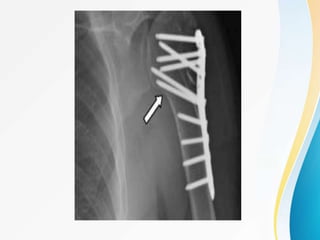

4-PART MARKED DISPLACEMENT, VARUS

MALALIGNMENT , FRACTURE DISLOCATION :

4 STEPS

• Incision through deltopectoral approach

• Reduction and preliminary fixation

• Plate fixation

• Rotator cuff tendon suturing to the plate .

STEP 3 :

• Attach plate to humeral shaft

• and fix the plate by passing a compression screw on the

shaft

• now make drill holes through drill sleeves into the humeral

head

• drill the near cortex only ,woodpecker drilling technique

• minimum of 5 screws placed

• check screw size under c-arm

• calcar screws are essential in all varus displaced fractures